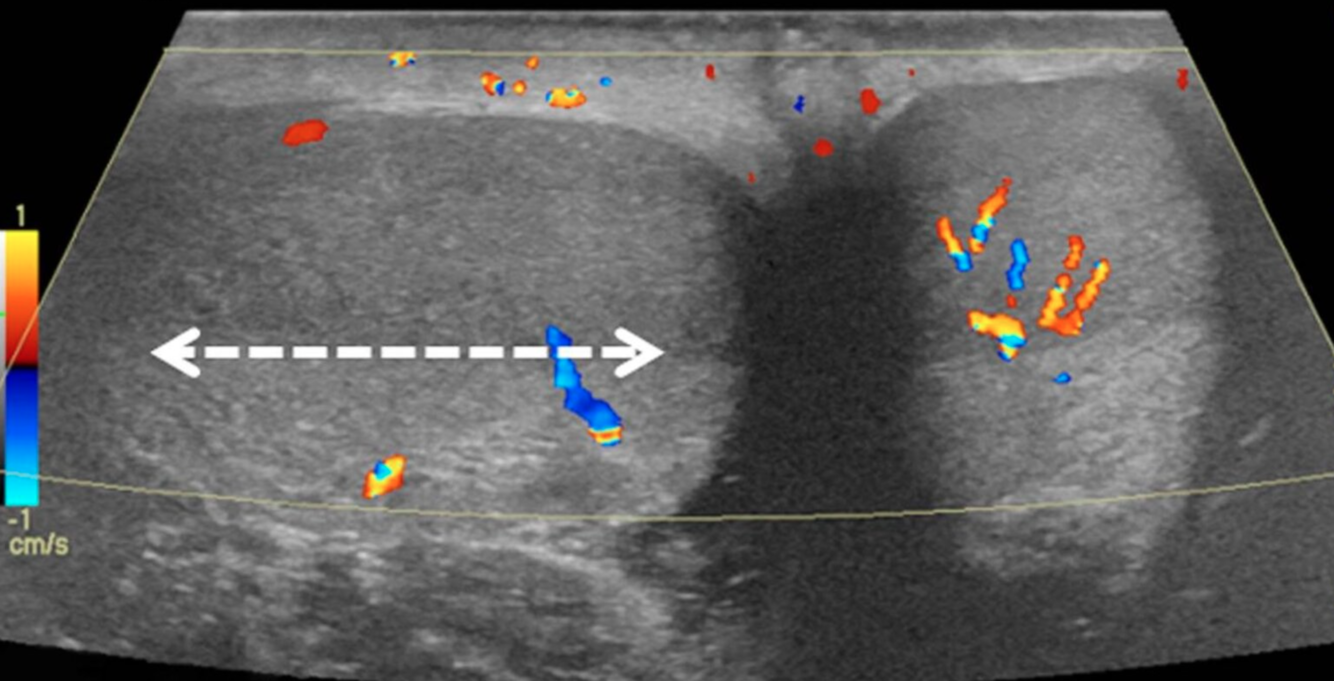

- Color Doppler ultrasound of both testes (transverse plane) of a 14-year-old boy who woke up with acute right scrotal pain

- The right testis lies in an abnormal horizontal position (white arrow), with intratesticular flow slightly reduced compared to the left testis.

- These findings are consistent with intermittent testicular torsion. During orchiopexy, a bell clapper deformity was seen bilaterally determined to be the most likely cause.